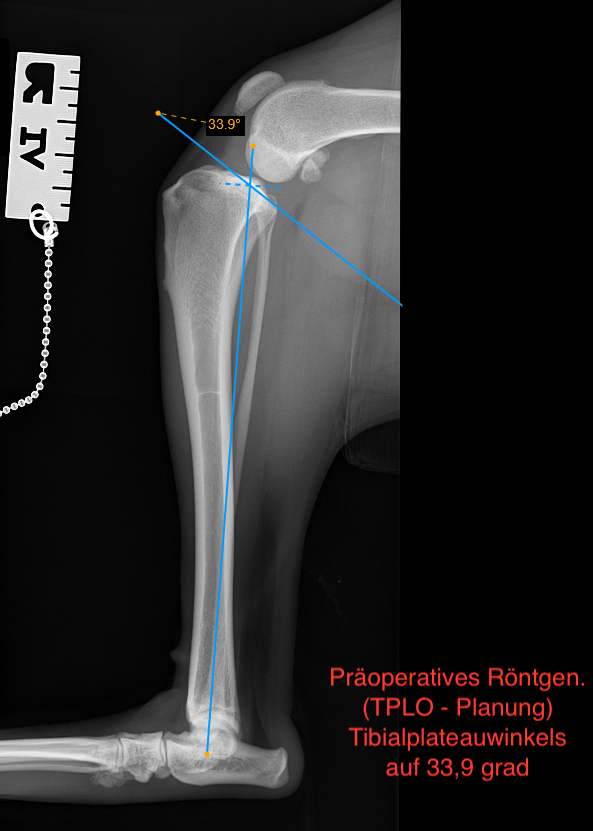

Die TPLO (Tibial Plateau Leveling Osteotomy) ist ein bewährtes Verfahren zur funktionellen Stabilisierung des Kniegelenks und ermöglicht eine zuverlässige und langfristige Verbesserung der Gelenkfunktion.